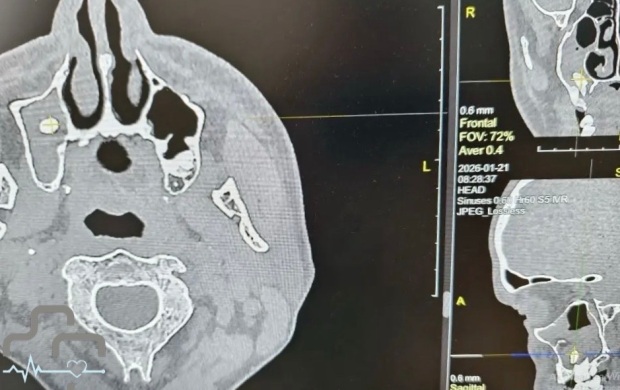

В Орске мужчина обратился в больницу с жалобами на затрудненное дыхание. Оказалось, что в его носовой пазухе оказался зуб. Об этом сообщили на странице во "ВКонтакте" городской больницы Орска.

Выяснилось, что ранее мужчина удалил зуб. В медучреждении объяснили, что такое случается, когда при удалении зуба происходит нарушение целостности костной перегородки, отделяющей зубной ряд от носовой пазухи, из-за чего зуб или его фрагмент могут сместиться в пазуху.

У пациента зуб проник так глубоко, что это повлияло на дыхание.